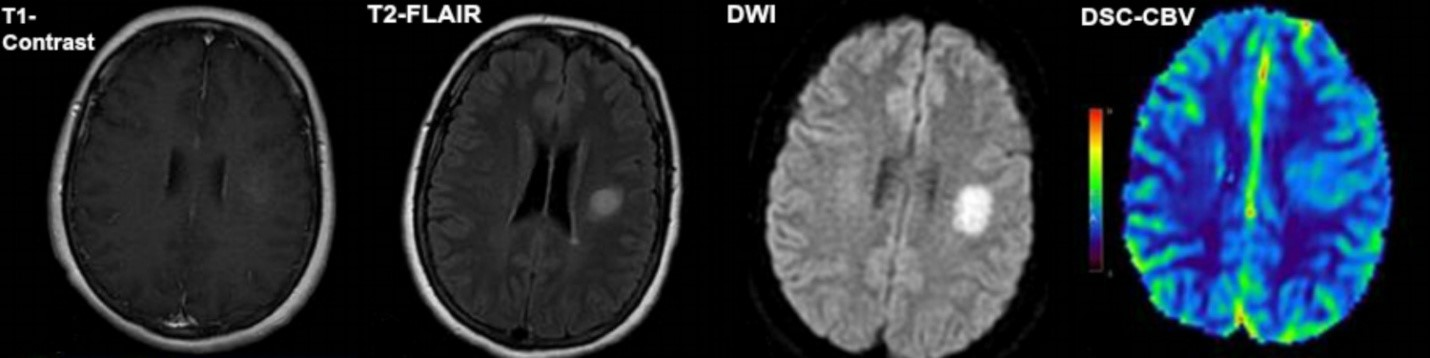

These are the four MR image types that will be analyzed in this study. These are all from the same brain, but each imaging sequence weights signal intensities differently. T1-contrast highlights enhancing tumor if it takes up the injected contrast agent. T2-FLAIR suppresses normal cerebral fluid signal, so abnormalities are more clearly delineated. In this case, the tumor is not contrast-enhancing, but it is FLAIR-enhancing. DWI highlights areas of restricted fluid diffusion, shown as the bright circle in the right side of the brain. DSC-CBV is a post-processed cerebral blood volume map that shows where there is the greatest density of blood in the brain, based on the passage of a contrast bolus. (Image source: http://www.sciencedirect.com/science/article/pii/S0150986114002296)